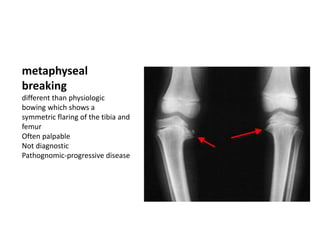

metaphyseal

breaking

different than physiologic

bowing which shows a

symmetric flaring of the tibia and

femur

Often palpable

Not diagnostic

Pathognomic-progressive disease